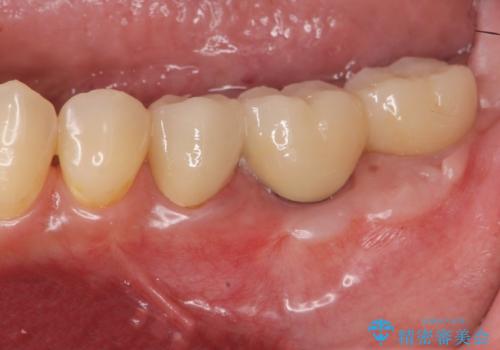

[メタルフリー] 虫歯・銀歯だらけの口腔内を全顎治療

![[メタルフリー] 虫歯・銀歯だらけの口腔内を全顎治療の症例 治療前](https://seimitsushinbi.jp/wp/wp-content/uploads/2025/03/e26a9887bc6905a2f0f51f5772b5ac9c-500x350.jpg?v=1741918285)

![[メタルフリー] 虫歯・銀歯だらけの口腔内を全顎治療の症例 治療後](https://seimitsushinbi.jp/wp/wp-content/uploads/2025/03/530cf6cca6451bc106a9fb69dd58908a-500x350.jpg?v=1741918343)